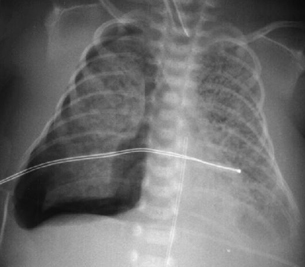

Fístula traqueoesofágica: sonda orogástrica torcida no esôfago

Do acervo de Ponthenkandath Sasidharan, MD; usado com permissão